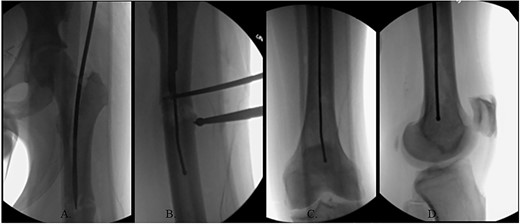

The patient was positioned supine on a fracture table. A guide wire was inserted through a 4-cm surgical incision proximal to the greater trochanter (GT) and was passed through a cannulated awl in a position slightly medial to the tip of the GT on the AP and center on the lateral (Fig. 2B). A (15-mm) entry reamer widened the opening (Fig. 2C). A rigid cannulated reduction rod and forceful malleting allowed the ball-tipped guidewire to cross the close reduced fracture, but too lateral and posterior distally (Fig. 3A and B). The cannulated flexible reamers encountered impassible blastic lesions within the proximal femur (Figs 3C and 5B).

(A) Cannulated awl positioned medial to tip of GT on the AP XR; (B) cannulated awl positioned center of GT on the lateral XR; (C) entry reamer over guide pin on the AP XR.

(A) Ball-tipped guidewire slightly lateral position at the knee on the AP XR; (B) ball-tipped guidewire too posterior at the knee on the lateral XR; (C) flexible reamer within the proximal femur abutting blastic lesions.

(A) Canulated cutter tool creating a new path in the proximal femur; (B) rigid canulated reduction rod directing the guidewire across a reduced fracture held with a proximal bone hook and distal ball spike pusher; (C) center positioned ball-tipped guidewire at the knee on the AP XR; (D) center positioned ball-tipped guidewire at the knee on the lateral XR.